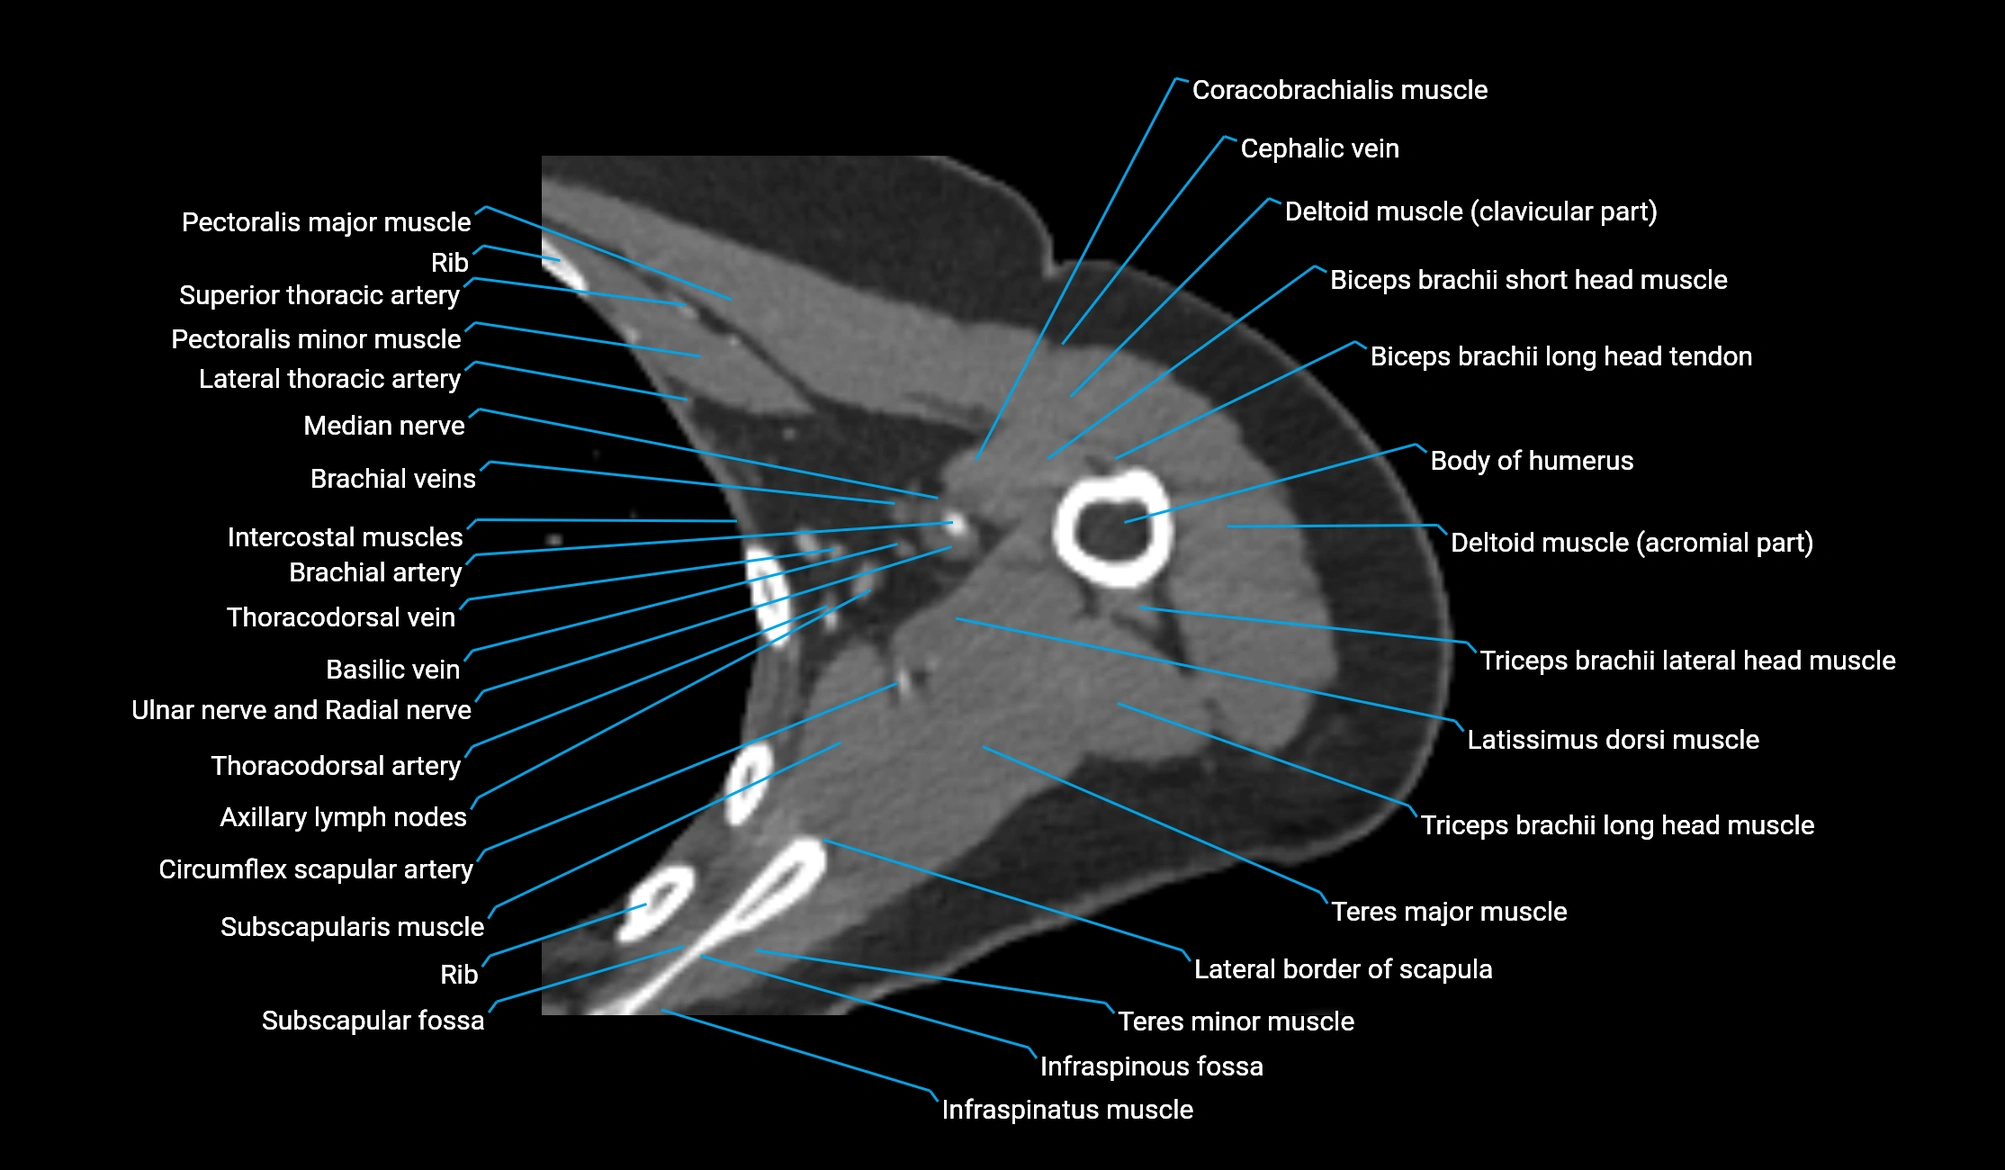

- Acromial part of deltoid muscle

- Clavicular part of deltoid muscle

- Coracobrachialis muscle

- Cephalic vein

- Circumflex scapular artery

- Axillary lymph nodes

- Infraspinatus muscle

- Infraspinous fossa

- Pectoralis major muscle

- Pectoralis minor muscle

- Subscapularis muscle

- Subscapular fossa

- Teres major muscle

- Teres minor muscle

- Lateral border of scapula

- Thoracodorsal artery

- Triceps brachii muscle

- Long head of triceps brachii muscle

- Lateral head of triceps brachii muscle